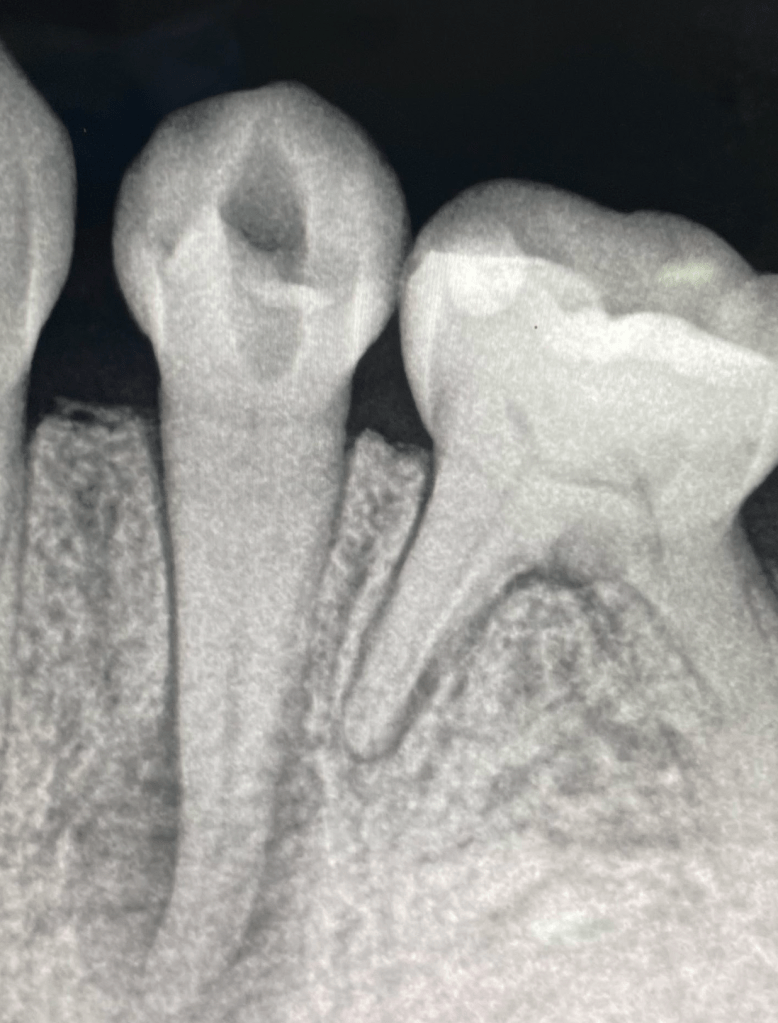

Endodoncia diente temporal, ausencia definitivo